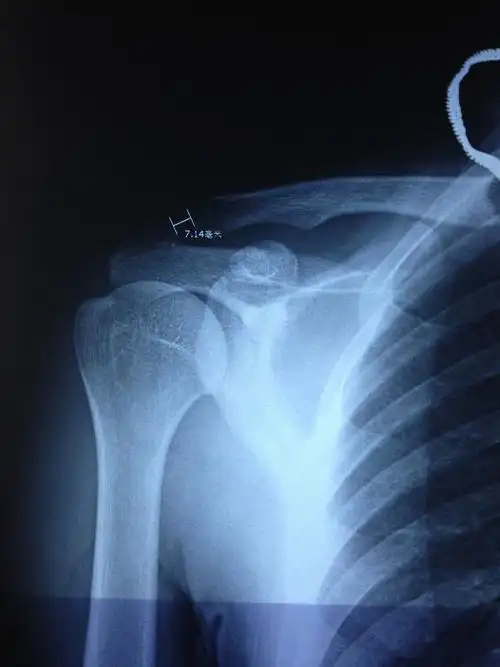

请问右肩锁关节半脱位能有多小几率能评上评残?